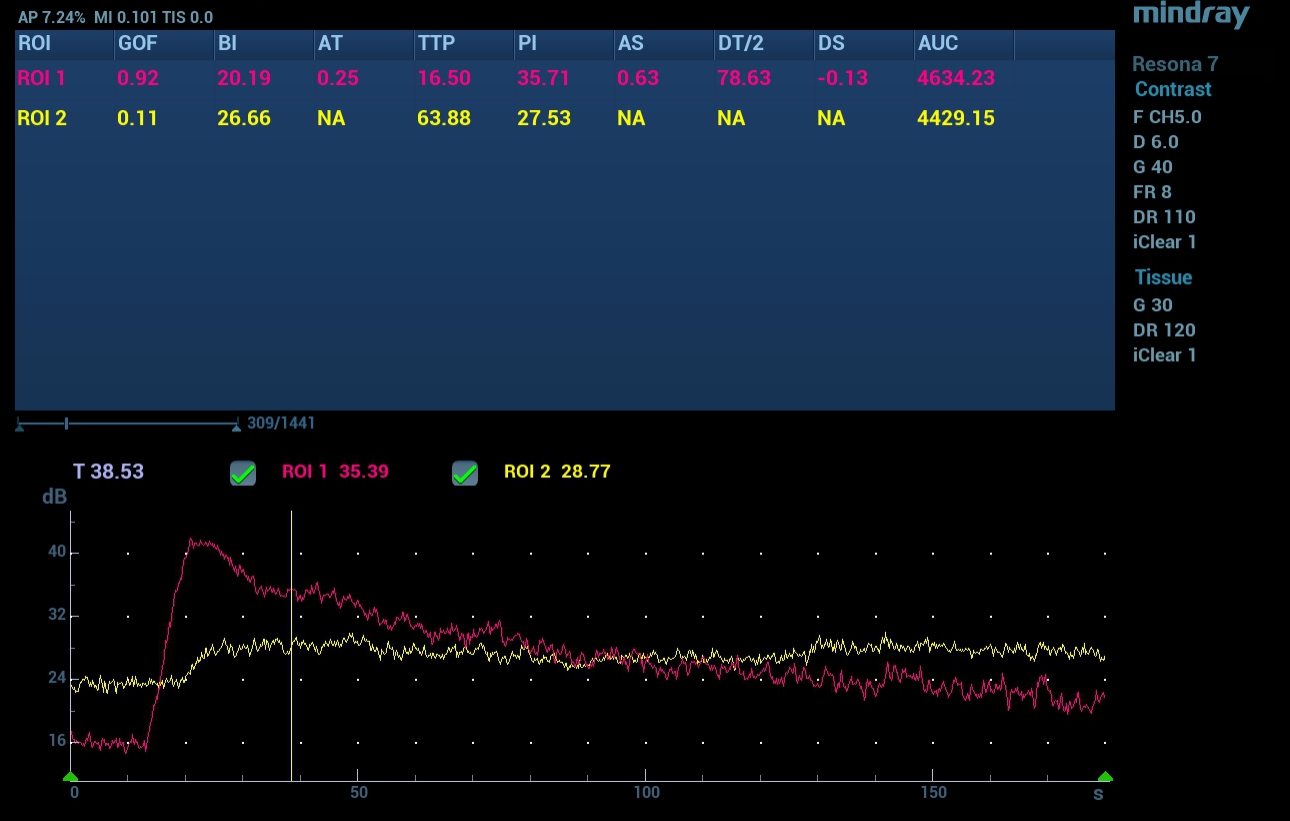

???? ??? ??( Contrast Imaging Quantification Analysis)

?? ??? ??-?? ??? ??? ??? ?? ?? ??? ??? ???? ???. ?? ??? ??? TTP 16.5?, PI 35.7dB, DT/2 78.6?, AUC 4634.2dB/? ????. ???? ?? ?? ??? ?? ??-?? ??? ???? ?? ? ?? ??? ??? ???? ??? TTP? 63.9?, PI? 27.5dB, AUC? 4429.2dB/? ????. DT/2 ????? ???? ?????(??? 5).